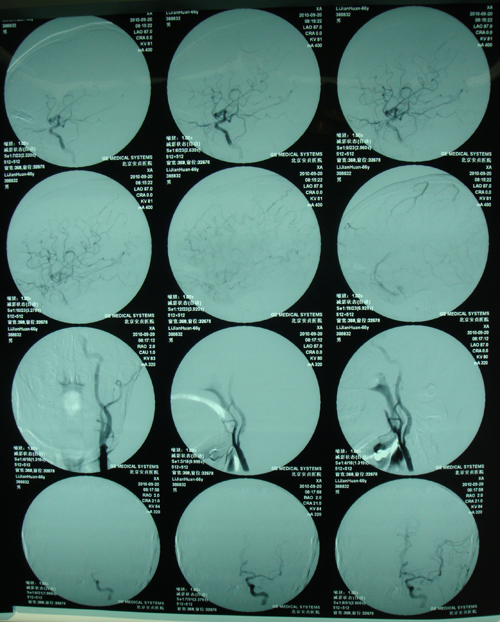

颈动脉+全脑血管造影:左侧颈内动脉近端节段性偏心性狭窄,考虑为动脉硬化性改变;右髂外动脉及股动脉未见异常。